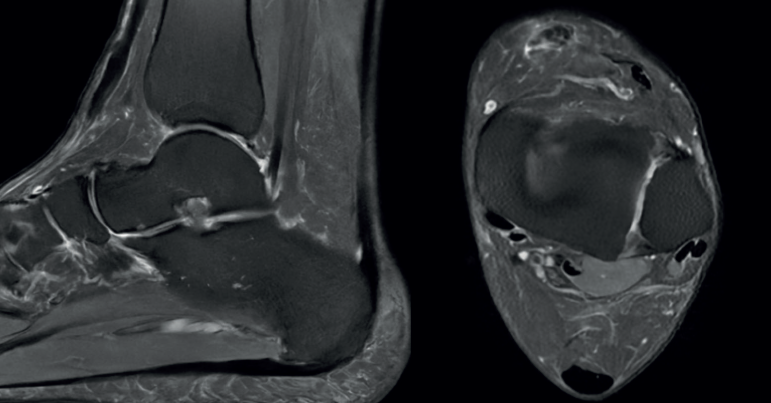

Los estudios radiográficos no arrojaron anormalidades, mientras que la resonancia magnética reveló una desinserción completa del tendón TA con retracción hasta la articulación tibiotalar (Figura 1). Se decide un tratamiento quirúrgico de reanclaje tendinoso primario.